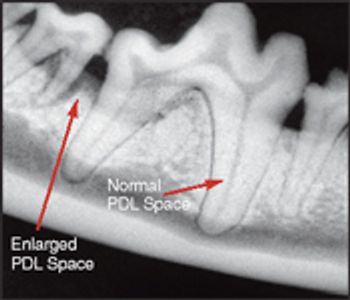

Intraoral radiographs are essential to perform quality dental therapy. Teeth can be cleaned and polished without seeing radiographic images below the gingiva, but "dentistry" cannot be performed properly.

According to industry estimates, less than 10 percent of small animal practices have dental radiograph units and of those, less than 10 percent take intraoral films on every dental case.